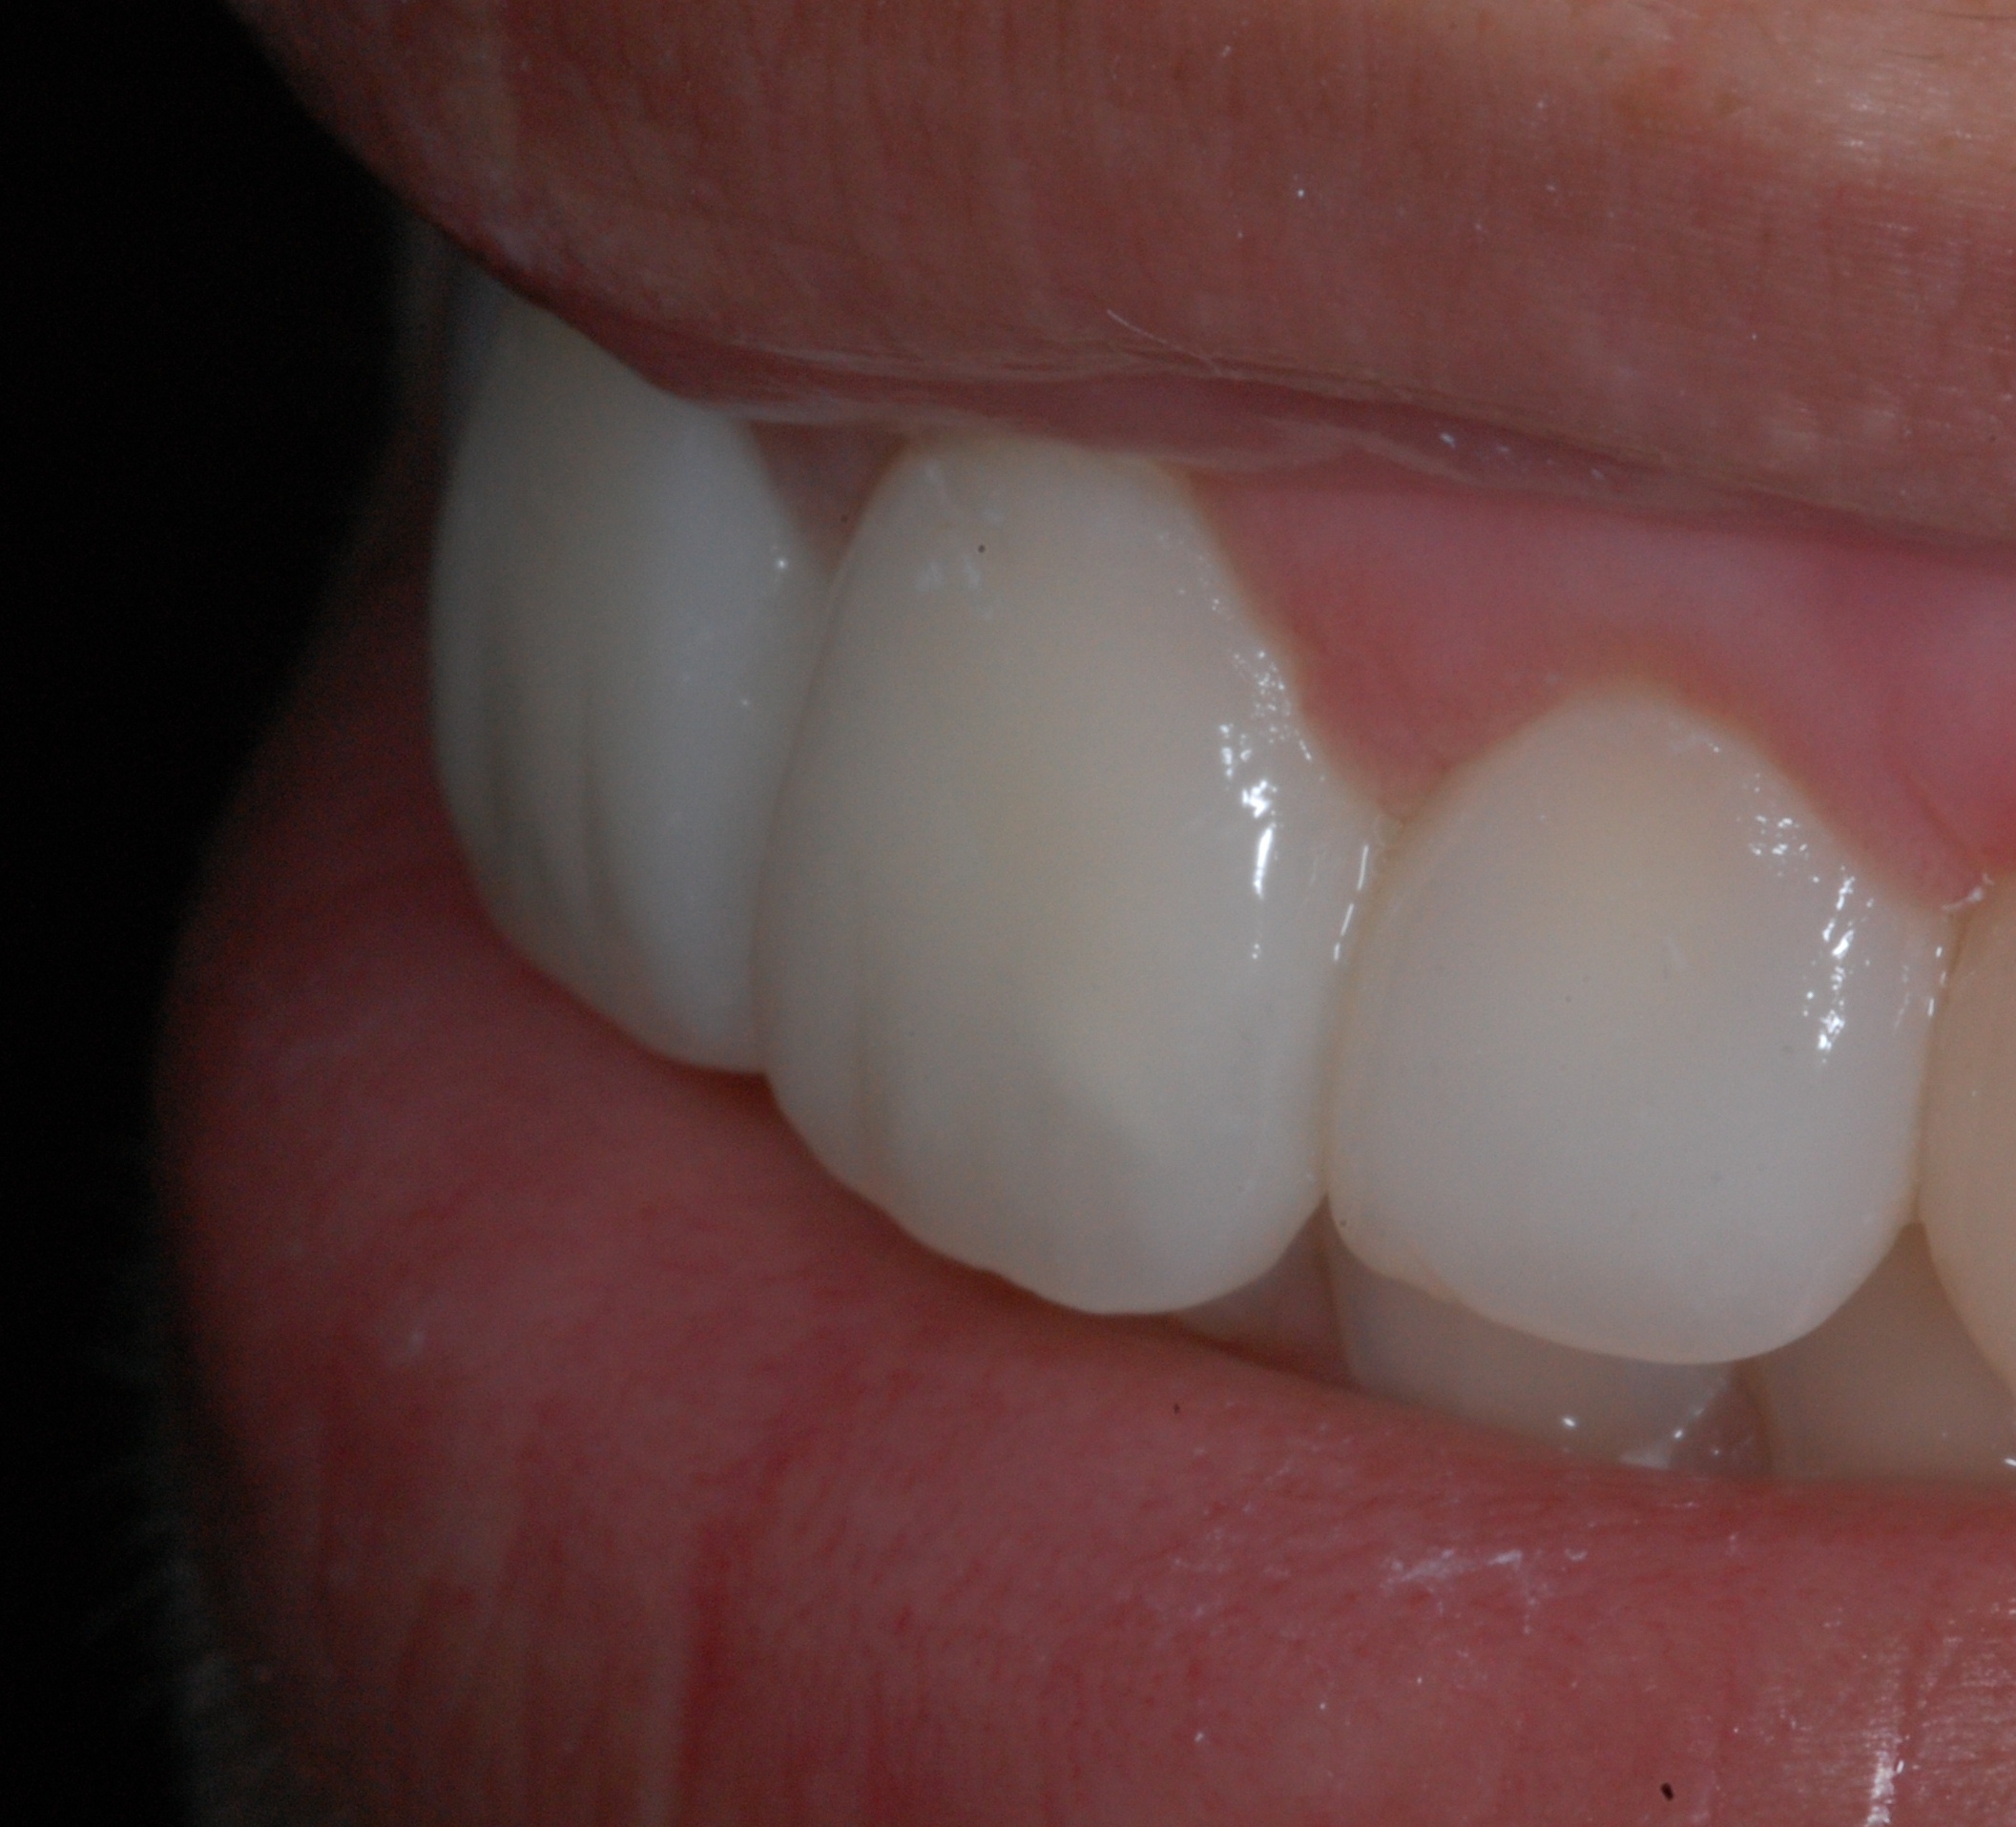

The presence of diastema, between anterior teeth, distorts a pleasing smile by concentrating the observer’s attention on the spaces. The patient’s needs and expectations must be considered in the process of treatment planning to ensure satisfaction with the treatment outcomes. There are many forms of therapy that can be used for diastema closure. A carefully developed diagnosis, which includes a determination of the causal elements and advanced treatment planning, allows the most appropriate treatment to be selected for each case. The aim of this paper is present a multidisciplinary approach as a solution to multiple diastemas in the anterior region using gingival tissue recontouring and direct adhesive restorations, with minimum wear of the dental structure, after the orthodontic intervention discussing the minimal intervention to obtain imperceptive and aesthetic final restoration. Thirty-six months after the treatment was carried out, the final aesthetic was maintained with all dental element details and gingival tissue harmony, without recurrence of periodontal pockets and the preservation of the tooth color and shape.